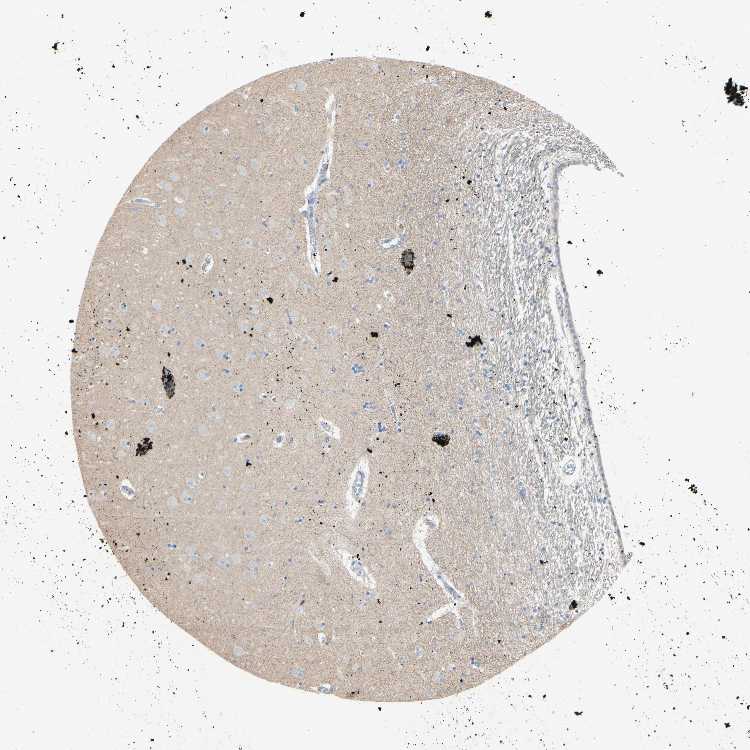

HIPPOCAMPUS - Antibody stainingi

Antibody staining in the annotated cell types in the current human tissue is reported as not detected, low, medium, or high, based on conventional immunohistochemistry profiling in selected tissues. This score is based on the combination of the staining intensity and fraction of stained cells.

Each image is clickable and will lead to virtual microscopy that enables deeper exploration of all samples and also displays staining intensity scores, fraction scores and subcellular localization as well as patient and tissue information for each sample.

Antibody HPA011081

Glial cells Not detected

Neuronal cells Not detected